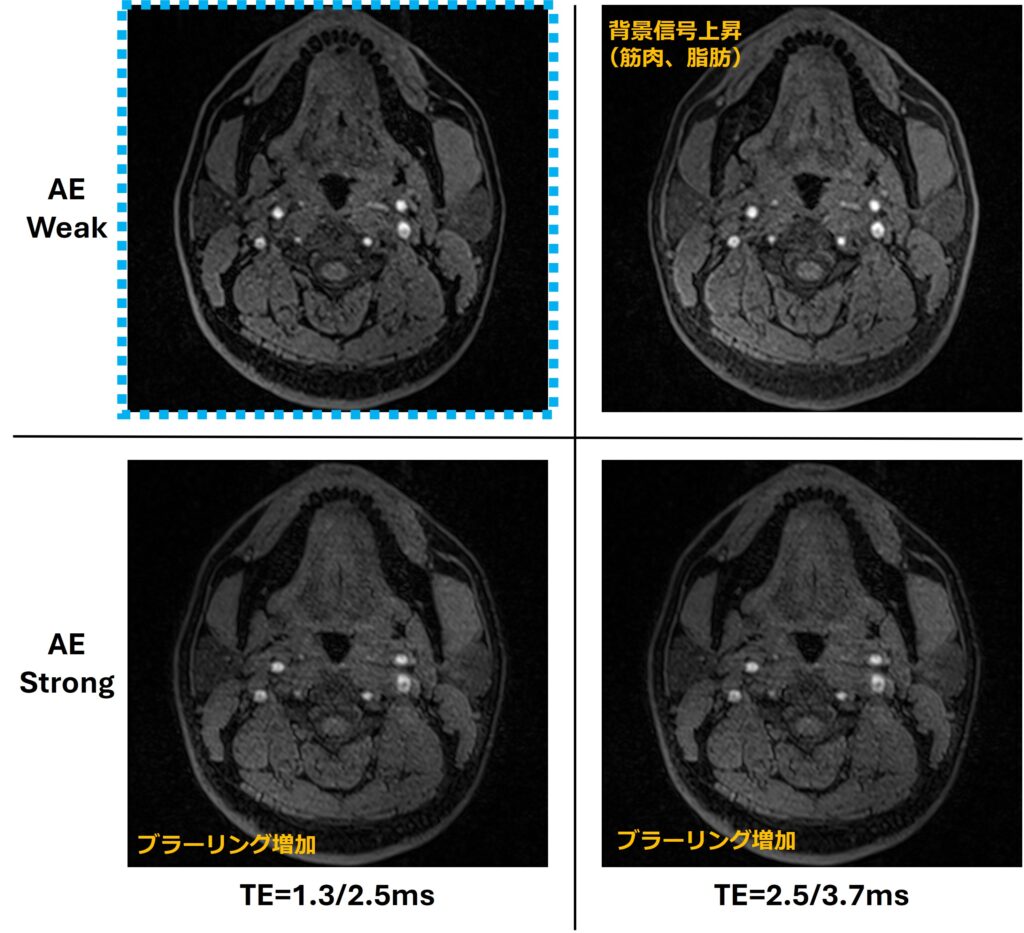

TEは空間分解能や受診バンド幅(BW)、グラディエントモード等のパラメータ調整で1.3/2.5ms、2.5/3.7ms…と複数の組み合わせが選択可能です。AEは収集エコー前半を打ち切ってTE短縮を図るテクニックでOff・Weak・Strongの3種があります。TrioのDixon-VibeではAEが強制的に適用されます。TEとAEの組み合わせによってトランケーションやブラーリングの増大、およびコントラスト変化など画質に影響を及ぼします1)。TEとAEの組み合わせによる画像の違いを示します。図の上下がAEの違い、左右がTEの違いとなります(Fig.3)。1.3/2.5msと比べると、2.5/3.7msでは皮下脂肪や筋肉信号が高いことがわかります。これはMIP時には不都合となります。AE強度に着目すると、StrongではWeakに比べて画像のブラーリングが目立つことがわかります。1.3/2.5ms使用時はかなりBWを上げる必要がありSNRの面で若干不利となります。ただ、血流信号の位相分散やステント等の磁化率の影響を低減する観点から、BWは広域でTEも短い方が有利と言えます。以上より「TEは1.3/2.5ms、AE強度はWeak」が最適と判断しました。